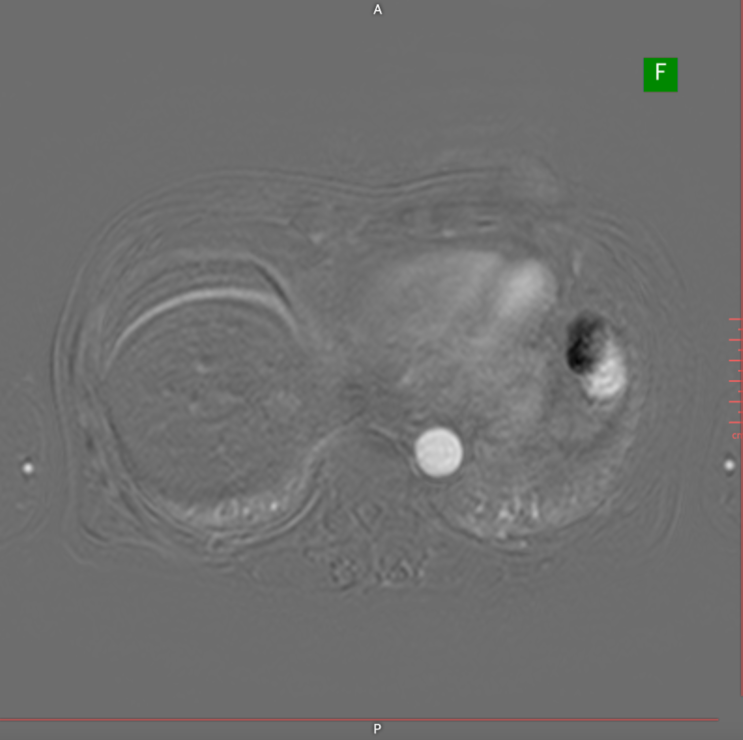

간암, 간염에 관련 사례를 확인하실 수 있습니다.